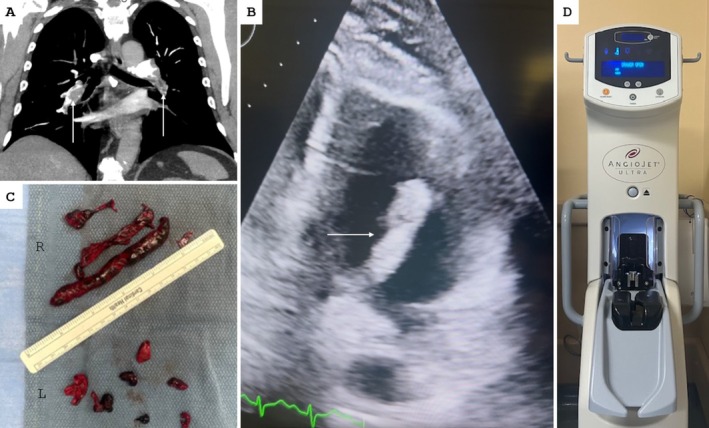

经皮肺血栓切除术使用AngioJet装置是一个可行的选择,用于管理急性肺栓塞与运输中的凝块在选定的高风险患者。需要进一步的大规模研究来更好地确定经皮取栓术治疗高危人群转运血栓的安全性和有效性。

Percutaneous pulmonary thrombectomy using the AngioJet device is a feasible option for the management of acute pulmonary embolism with a clot in transit in selected high-risk patients. Further large-scale studies are needed to better establish the safety and efficacy of percutaneous thrombectomy for clot in transit in high-risk populations.